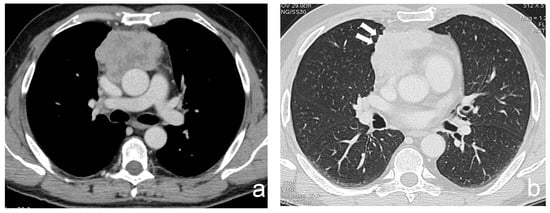

Figure 2.

(a,b) A 63-year-old man with a poor differentiated squamous thymic carcinoma invading the pericardium and the lung (stage IIIa). Margins of the lesion are multilobulated and indented at the interface with the lung; the latter CT finding is better demonstrated using a lung window (arrows).

Some authors tried to correlate CT morphological features with clinical information and Masaoka–Koga and WHO classifications. Han X. et al. analyzed 159 patients with thymomas who underwent preoperative CT and found that tumor size and pleural effusion were associated with patient’s symptoms; moreover, high risk (B2 and B3) and stage III and IV thymomas were larger, with calcifications and irregular contours, and showed infiltration of vessels and mediastinal fat if compared with low-risk (A, AB, B1) and stage I and II lesions. Contours, abutment ≥ 50% of mediastinal structures and adjacent lung abnormalities were risk factors for metastases and recurrence [11]. Kato T. et al. investigated 53 patients with Masaoka stage I to III thymoma and 5 patients with stage IVa with 6 cases of pleural recurrence within 76 months of follow-up. Tumor diameter and contact length between the tumor and the lung were measured, and they found that the contact was significantly longer in the group with pleural recurrence, whereas tumor diameter was not significantly different between recurrence and non-recurrence group [12]. Shen Y. et al. investigated the possibility of predicting stage III thymoma with CT, analyzing 66 patients, and they found that for pleural and pericardial invasion, an absence of space between the tumor and pleura/pericardium with pleural/pericardial effusion and thickening showed a specificity of 100%. A multilobular tumor convex to the lung with adjacent abnormalities was highly specific for lung invasion, whereas for vessel invasion, specificity was 100% for tumors abutting ≥ 50% of the vessel circumference [13]. Regarding lung invasion, Green D.B. et al. enrolled 54 patients with thymoma, evaluating the interface between tumor and adjacent lung parenchyma. According to Shen Y. et al., they found that multilobulated thymomas were more likely to invade the lung; however, specificity increased significantly using the criterion of multilobulation with at least one acute angle among them [14] (Figure 2). The capability to predict lung invasion on preoperative imaging is pivotal for surgical planning because lung invasion may require a wedge resection and diaphragmatic plication due to phrenic nerve involvement [15]. In the same way, the evaluation of vascular infiltration is pivotal when establishing a surgical plan and assessing its feasibility. Direct signs of vascular involvement include vascular encasement, endoluminal soft tissue and irregular lumen contour [16].